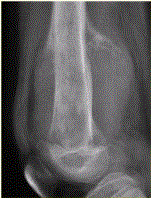

问题 患者男,16岁,左大腿下部疼痛伴肿胀2个月,逐渐加重。自感左膝上方胀痛,尤以夜间为著,伴行走困难。既往史及家族史无特殊。查体:左大腿下部明显肿胀,皮温较对侧升高。碱性磷酸酶明显增高。股骨平片及MRI见下图。 你认为对定性诊断有价值的征象是

选项 A.病变边缘模糊,内部信号不均 B.病变边缘骨皮质完整 C.病变周围可见软组织肿块 D.病变边缘可见骨膜反应,Codman三角形成 E.MR示病变周围骨髓明显水肿 F.病变内未见钙化影

答案 ACDEF